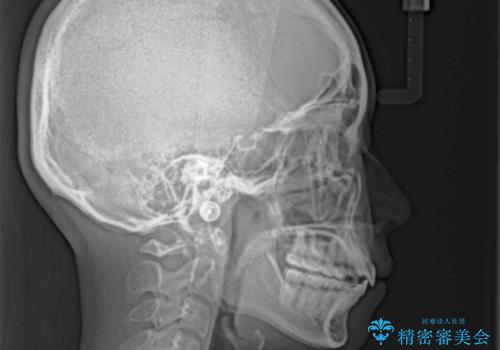

インビザライン特有の、奥歯の咬み合わせの問題もなく、しっかりと歯列を改善することができました。

舌側転位している上顎側切歯(内側に引っ込んでいる真ん中から2番目の歯)は、インビザラインが最も移動を苦手とする歯であり、これ以上の改善を望まれる場合にはワイヤー矯正、あるいはワイヤー矯正の併用をお勧めいたします。